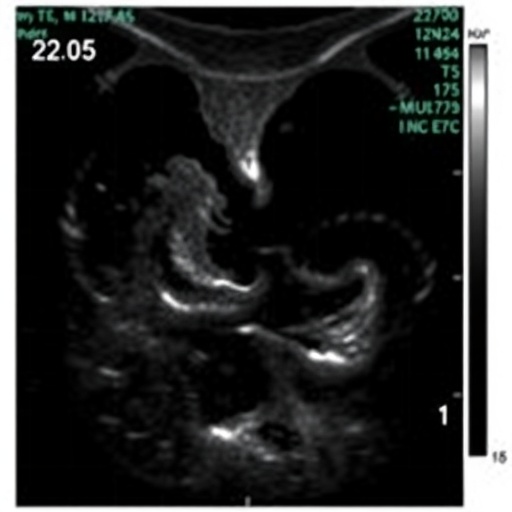

Utilizing high-resolution, prospective echocardiographic assessment, the study enrolled a cohort of infants diagnosed prenatally or shortly post-birth with CDH. Serial cardiac evaluations were meticulously performed in the immediate neonatal period, focusing on parameters such as right ventricular systolic pressure, tricuspid annular plane systolic excursion (TAPSE), and left ventricular ejection fraction. These metrics offer quantitative insights into the hemodynamic burden imposed by pulmonary vascular resistance and ventricular interdependence, both of which are pivotal in modulating clinical outcomes.

Moreover, the assessment of the interventricular septal configuration revealed critical insights into ventricular interaction. Altered septal geometry during systole and diastole suggested ventricular interdependency disruption, which clearly predicted hemodynamic instability. This mechanistic understanding advances neonatal care by pinpointing which patients are at escalated risk for cardiovascular collapse and may benefit from early pharmacological or surgical interventions targeting pulmonary vascular resistance.

Additional echocardiographic indicators, such as diminished TAPSE values, also emerged as predictors of adverse short-term outcomes. TAPSE, a measure of longitudinal right ventricular function, appeared instrumental in detecting subclinical ventricular dysfunction before overt heart failure manifestations. The use of this non-invasive parameter positions echocardiography as not only diagnostic but also prognostic, aligning with precision medicine paradigms in neonatal care.

Notably, the authors highlighted the potential for novel echocardiographic technologies, including speckle-tracking and three-dimensional imaging, to further enhance the characterization of cardiac mechanics in CDH. Such advanced modalities could augment the predictive accuracy and offer more nuanced insights into myocardial deformation patterns, expanding the clinical utility of bedside cardiac ultrasound.